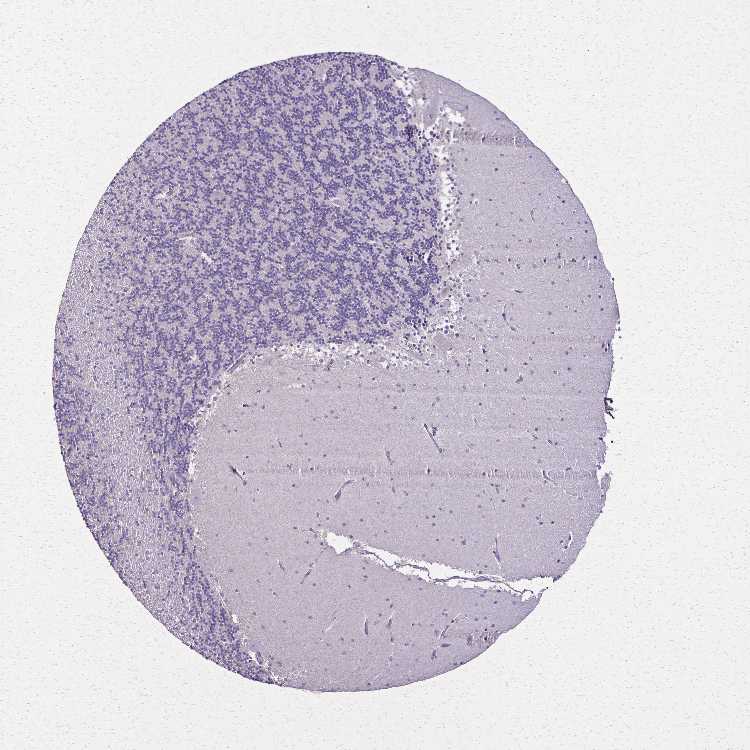

BRAIN CEREBELLUM Show tissue menu

CEREBELLUM - Expression summary

CEREBELLUM - Antibody stainingi

Antibody staining in the annotated cell types in the current human tissue is reported as not detected, low, medium, or high, based on conventional immunohistochemistry profiling in selected tissues. This score is based on the combination of the staining intensity and fraction of stained cells.

Each image is clickable and will lead to virtual microscopy that enables deeper exploration of all samples and also displays staining intensity scores, fraction scores and subcellular localization as well as patient and tissue information for each sample.

Antibody HPA063007

Purkinje cells Not detected

Cells in granular layer Not detected

Cells in molecular layer Not detected